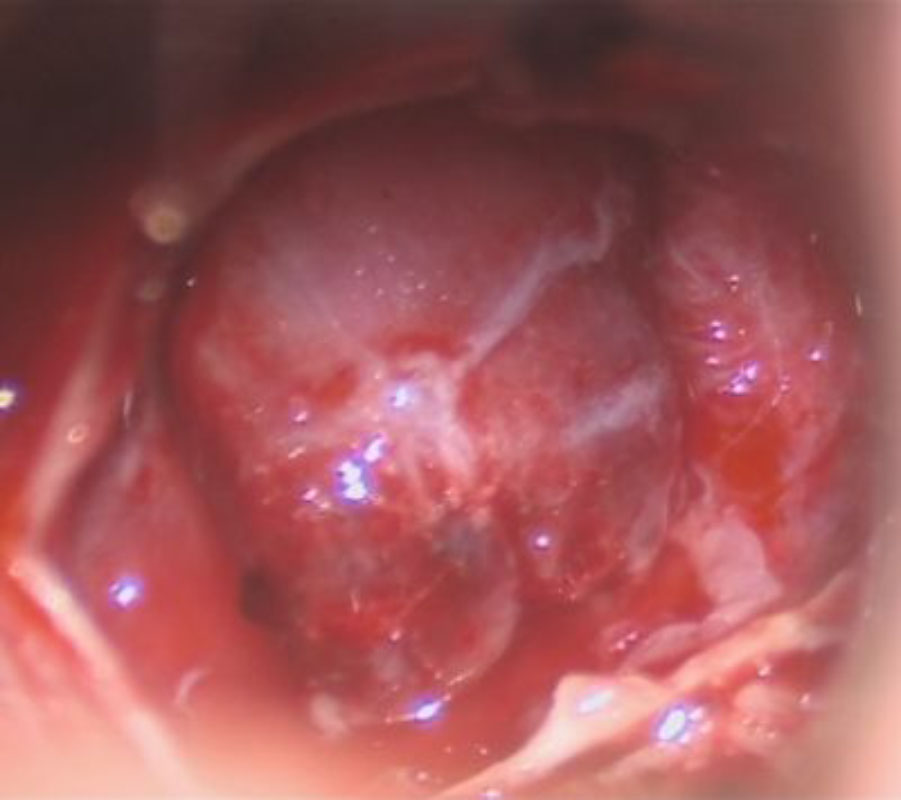

No.’25_108 摘出 前

No.’25_108  摘出 中

No.’25_108 摘出 後